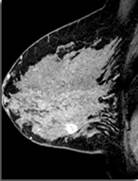

IRM préopératoire dans le cancer du sein : un bilan globalement positif

Afin d'éviter la multiplication des interventions chez les patientes atteintes d'un cancer du sein primitif (CSP), une évaluation préthérapeutique bilatérale est nécessaire. Comparée à la mammographie (MG) et à l'échographie (EG), l'imagerie par résonnance magnétique (IRM) permet de réaliser un bilan d'extension plus précis et de détecter les microlésions carcinomateuses occultes dans le sein homo- et contro-latéral. De plus, elle autorise une meilleure gradation (« staging ») locale par rapport à la MG et à l'EG. Cependant, l'intérêt de l'IRM pré-opératoire (IRMPO) est actuellement débattu. En effet, les résultats de l'IRMPO peuvent modifier le schéma thérapeutique, et ces modifications ne sont pas toujours dans l'intérêt des patientes, l'exemple type étant celui des interventions (biopsies) inutiles sur des tumeurs bénignes.

Voici les résultats d'une étude récente dont l'objectif était d'évaluer le rapport bénéfice/risque de l'IRMPO dans le CSP. Elle a inclus 119 patientes ayant bénéficié d'une IRMPO bilatérale des seins entre juillet 2005 et août 2008 dans le cadre de la gradation d'un CSP. Les modifications de la prise en charge liées aux résultats de l'IRMPO ont été notées. Les lésions détectées par IRM ont été confrontées aux résultats histologiques. Les lésions supplémentaires malignes détectées par IRM et les biopsies complémentaires épargnées grâce aux résultats (négatifs) de l'IRM ont été considérées comme des résultats positifs (bénéfice). Par contre, les biopsies des tumeurs bénignes détectées par l'IRM ont été considérées comme des résultats négatifs (risque).